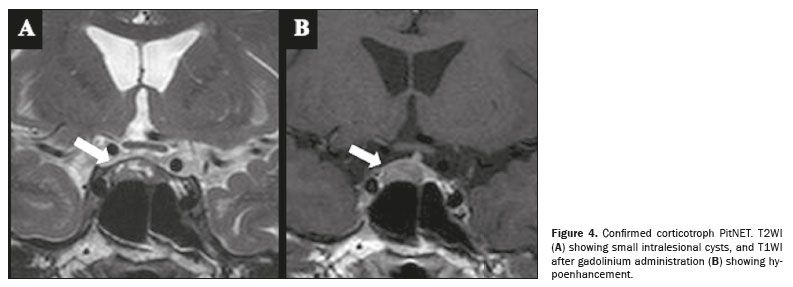

Silent corticotroph PitNETs typically present as macroadenomas and are more aggressive than other nonfunctioning types. A finding of multiple cysts on T2WI strongly suggests this subtype, with a sensitivity of 58% and specificity of 93% (Figure 4). These tumors show higher rates of preoperative hypopituitarism, cavernous sinus invasion, and early recurrence

(46).